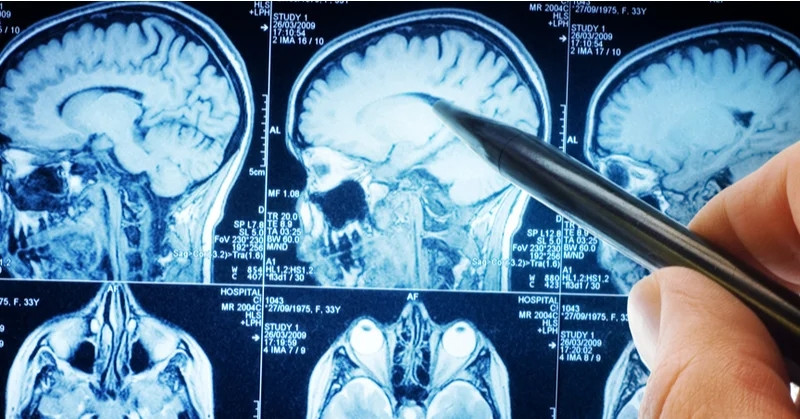

Điện tâm đồ ghi nhận tim của bà Sam xuất hiện hiện tượng ngoại tâm thu – một dạng loạn nhịp tim. Tình trạng này thường vô hại nhưng đôi khi có thể nguy hiểm. Nữ bệnh nhân làm thêm xét nghiệm máu và chụp CT vì từng bị chấn thương đầu.

Kết quả gây sốc: Bà Sam có một khối u não. “Đầu tôi quay cuồng. Tôi gọi cho chị gái trong hoảng loạn và buộc phải đối diện với sự hữu hạn của chính mình. Tôi ngủ trong tư thế ngồi, sợ sẽ không tỉnh dậy”, bà Sam nhớ lại.

Vì vị trí khối u, bác sĩ không thể phẫu thuật. Dù nhiều khả năng lành tính, u có thể ảnh hưởng đến thị lực, giọng nói và gây co giật. Sam phải uống thuốc hằng ngày, chụp MRI não hằng tháng. Năm 2022, bà còn trải qua thủ thuật điều trị loạn nhịp tim.